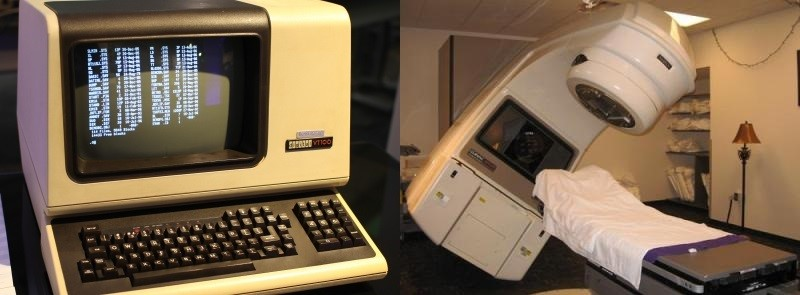

Во-первых, это череда трагических событий, к которым привели ошибки в аппарате лучевой терапии Therac-25. С июня 1985 года по январь 1987 года этот аппарат стал причиной как минимум шести передозировок радиации, некоторые пациенты получили дозы в десятки тысяч рад. Как минимум двое умерли непосредственно от передозировок. Причиной трагедий были ошибки в программном обеспечении аппарата, а принципиальной проблемой была неверная стратегия обеспечения безопасности.